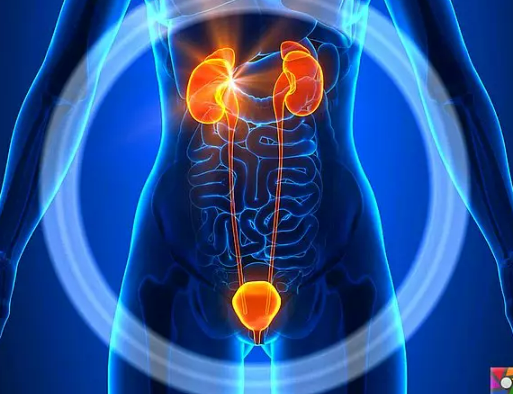

İdrar Yolu Enfeksiyonu Nedir?

İdrar yolu enfeksiyonu (İYE), mesane, üretra, üreterler veya böbreklerin bir enfeksiyonudur. En yaygın enfeksiyon türlerinden biridir ve kadınların yaklaşık yüzde 40’ında ve erkeklerin yüzde 12’sinde hayatlarının bir noktasında görülür.

İdrar yolu, idrarı yapmaktan ve depolamaktan ve vücuttan atmaktan sorumludur. Bu süreç tekrar tekrar, genellikle günde birkaç kez gerçekleşir. Ancak idrar yolu aynı zamanda bakterilerin girip çoğalabileceği bir yerdir.